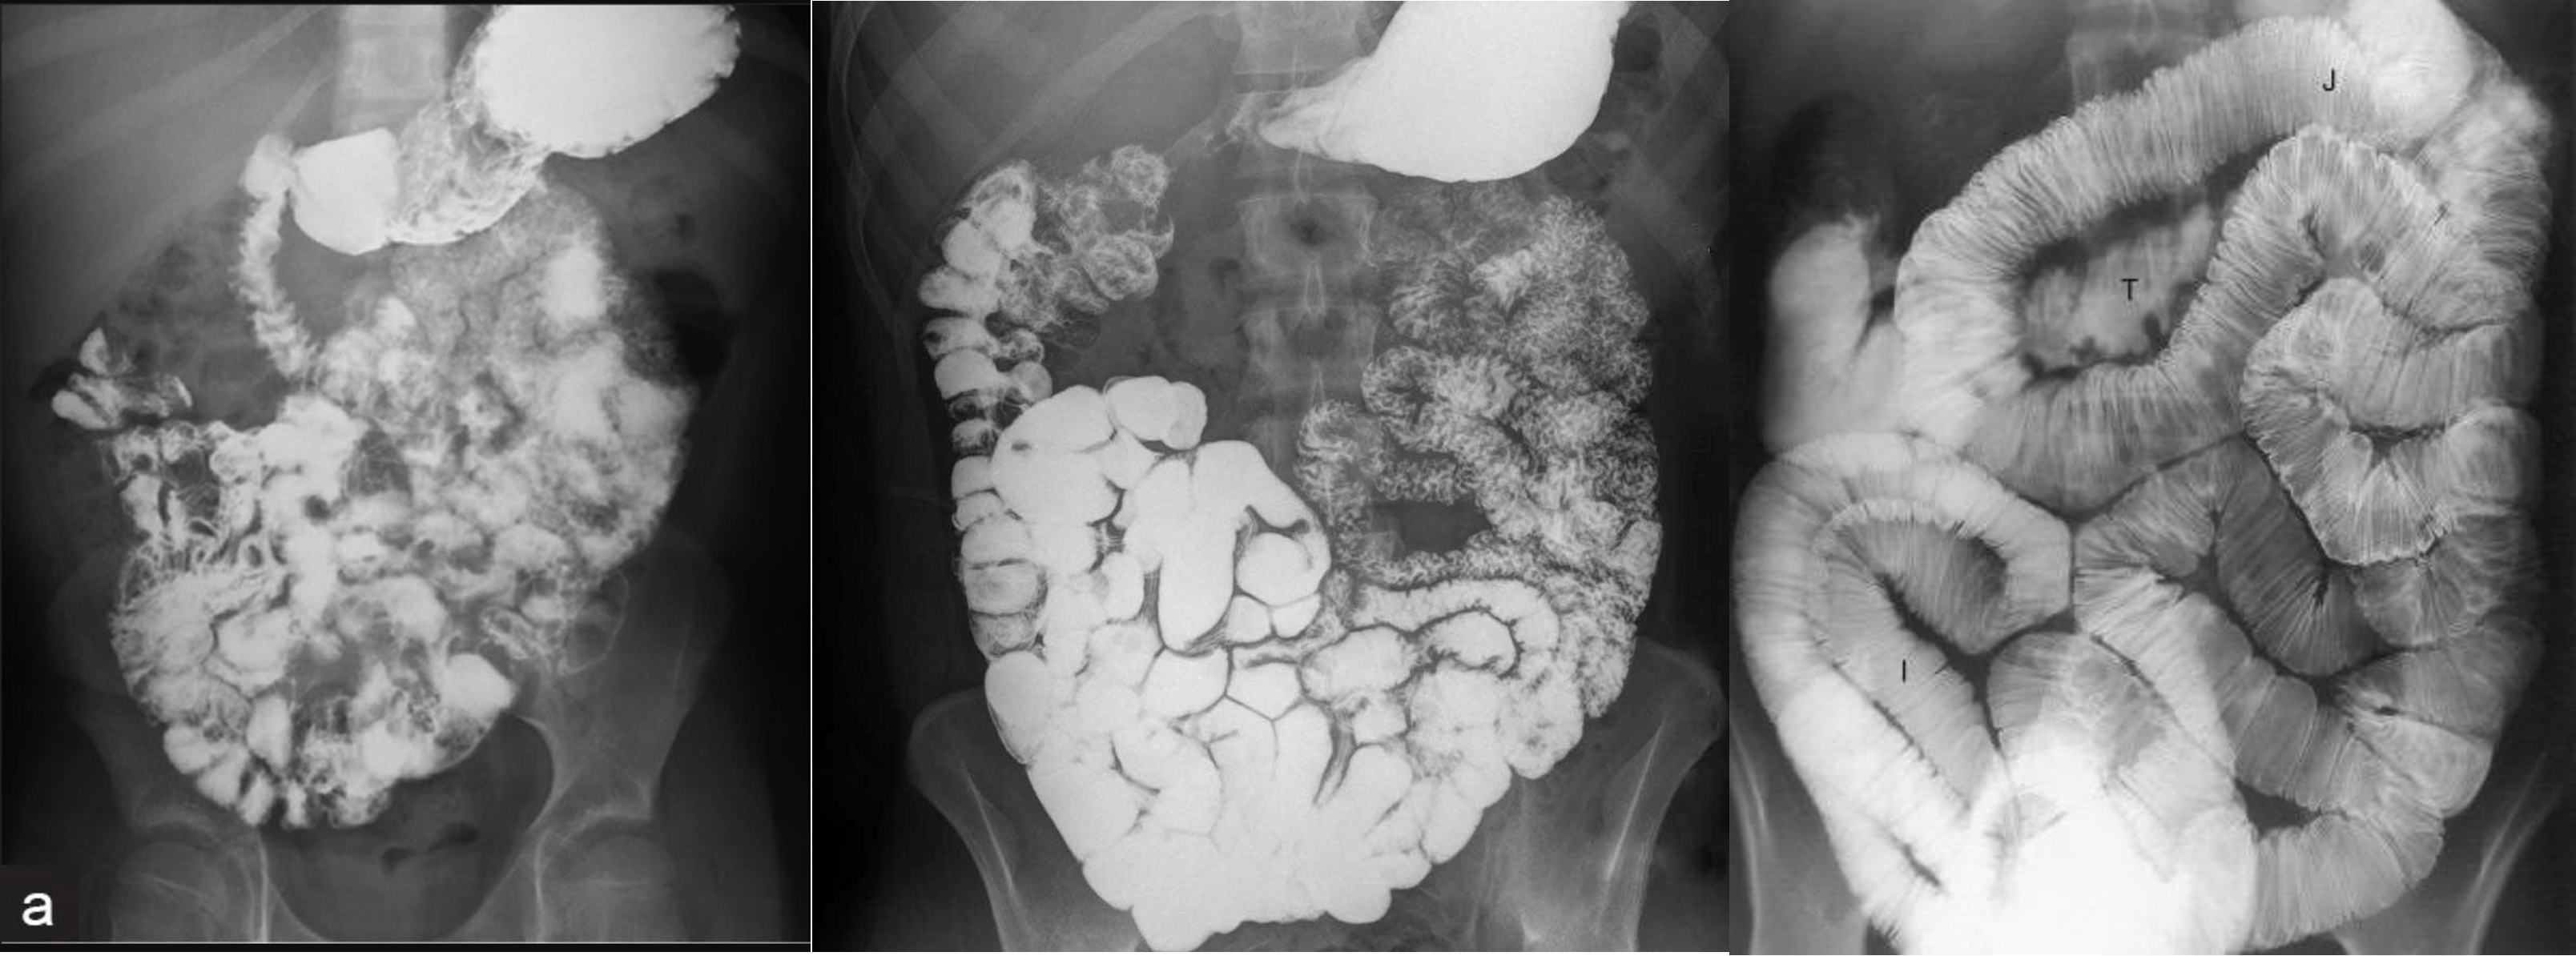

- follow through normal

- follow through (diff celiac; villus atrophy)

- barium enema from below

- apple core - neck and shoulder - stricture (cancer)

- Ulcerative collitis loss of haustration

- double enema - polyps